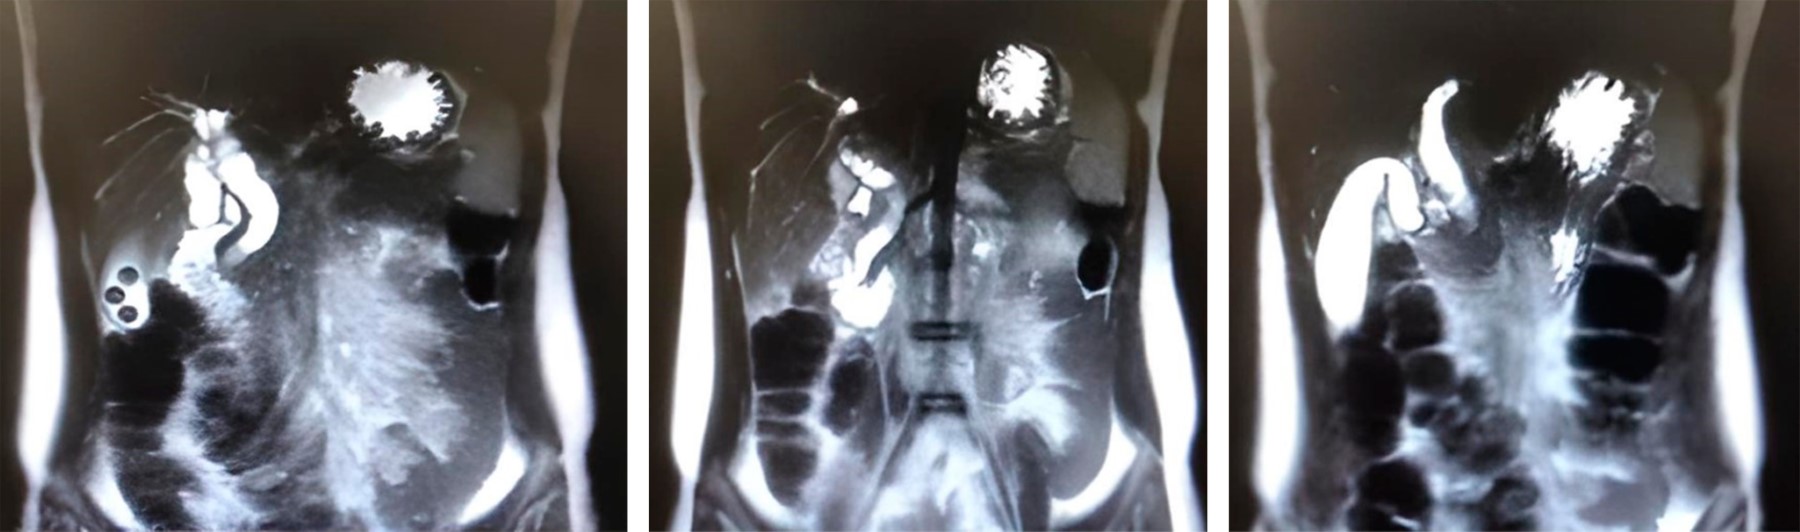

Dos días después, el paciente mostró aumento de su tinte íctérico en mucosas y piel y persistencia de dolor en hipocondrio derecho. Una nueva CRM reveló distención vesicular importante (diámetro longitudinal de 88 mm) con presencia de dos cálculos de 8 mm, el colédoco con aumento de su diámetro proximal (calibre máximo 13 mm), y disminución de su lumen distal (porción intramural), con una imagen hipointensa (5 mm) que podría corresponder a cálculo neumobilia, además de dilatación de la vía intrahepática (Figura 1).

Figura 1